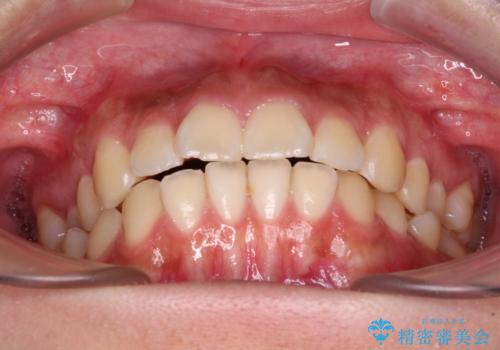

- 口元から飛び出てしまう前歯を気にして来院された患者様です。

上下前歯が嘴のように前方に突出しており、唇が閉じにくい状態であったため、上下左右の第一小臼歯4本を抜歯して、口元の突出感を改善することとしました。

口元の印象が劇的に解消され、気にしていたガミースマイルも図らずも改善することができました。